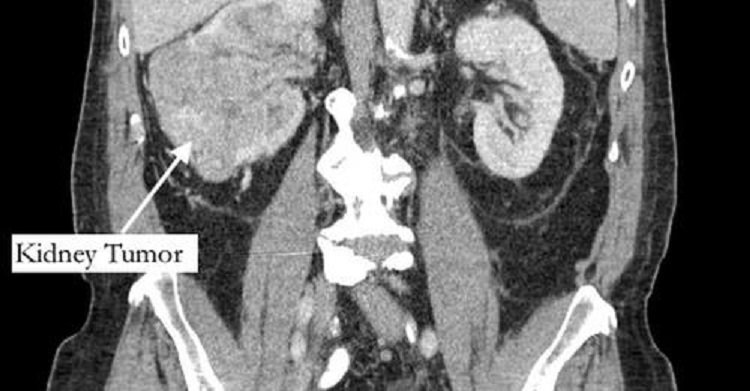

Segundo o jornal “New York Post”, Richard Bernstein, 42, sentia a dor havia cinco anos, e pensava que se tratava de uma fratura, mas recebeu o diagnóstico de grande tumor no rim e de um trombo tumoral, um tumor que se estende até um vaso sanguíneo.

O exame, encaminhado a um urologista, identificou ainda um trombo (coágulo no sangue) que cresceu através da veia renal e preenchia a veia cava, que drena sangue para o coração, e tinha 99% das artérias da coronária bloqueadas, além do fígado quase entrando em falência.

Segundo o diretor de urologia do Hospital Phelps, no estado de Nova York, Michael Grosso, o bloqueio de veias por conta do tumor e do trombo era o que explicava a dor no pé do aposentado, já que os sintomas de câncer no fígado costumam surgir já em uma fase avançada do tumor.

O paciente passou então por uma cirurgia de urgência para remover o tumor.

Após 12 horas de uma cirurgia complexa e casada entre médicos de diferentes especialidades, o tumor e o trombo foram retirados e uma ponte de safena foi realizada.